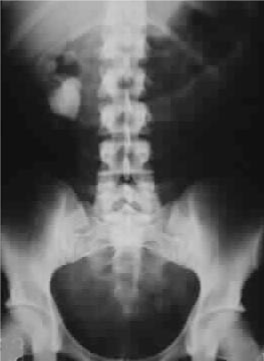

Amongst patients with symptomatic disease kidney stones are the commonest clinical feature. Renal stones and ureteric colic are significantly more frequent in younger patients where hypercalciuria (a high level of calcium in the urine) is commoner. However, kidneys stones may also be present with no symptoms, thus justifying ultrasonographic renal assessment in patients with proven pHPT.

Kidney stones